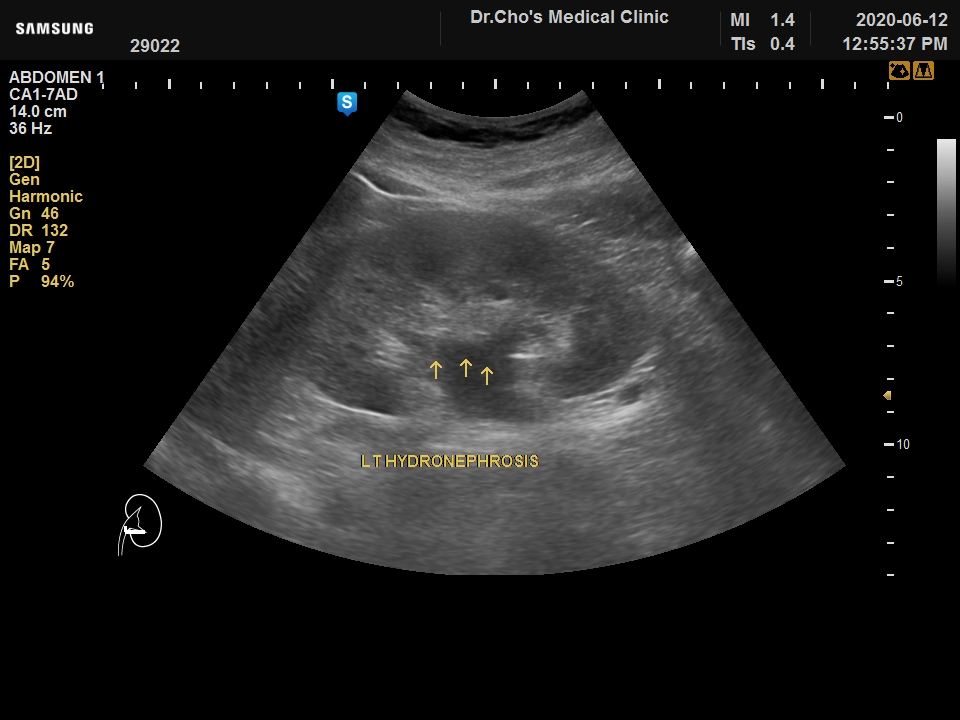

ÃÊÀ½ÆÄ°¶·¯¸®

¿ä·Î°á¼® ...